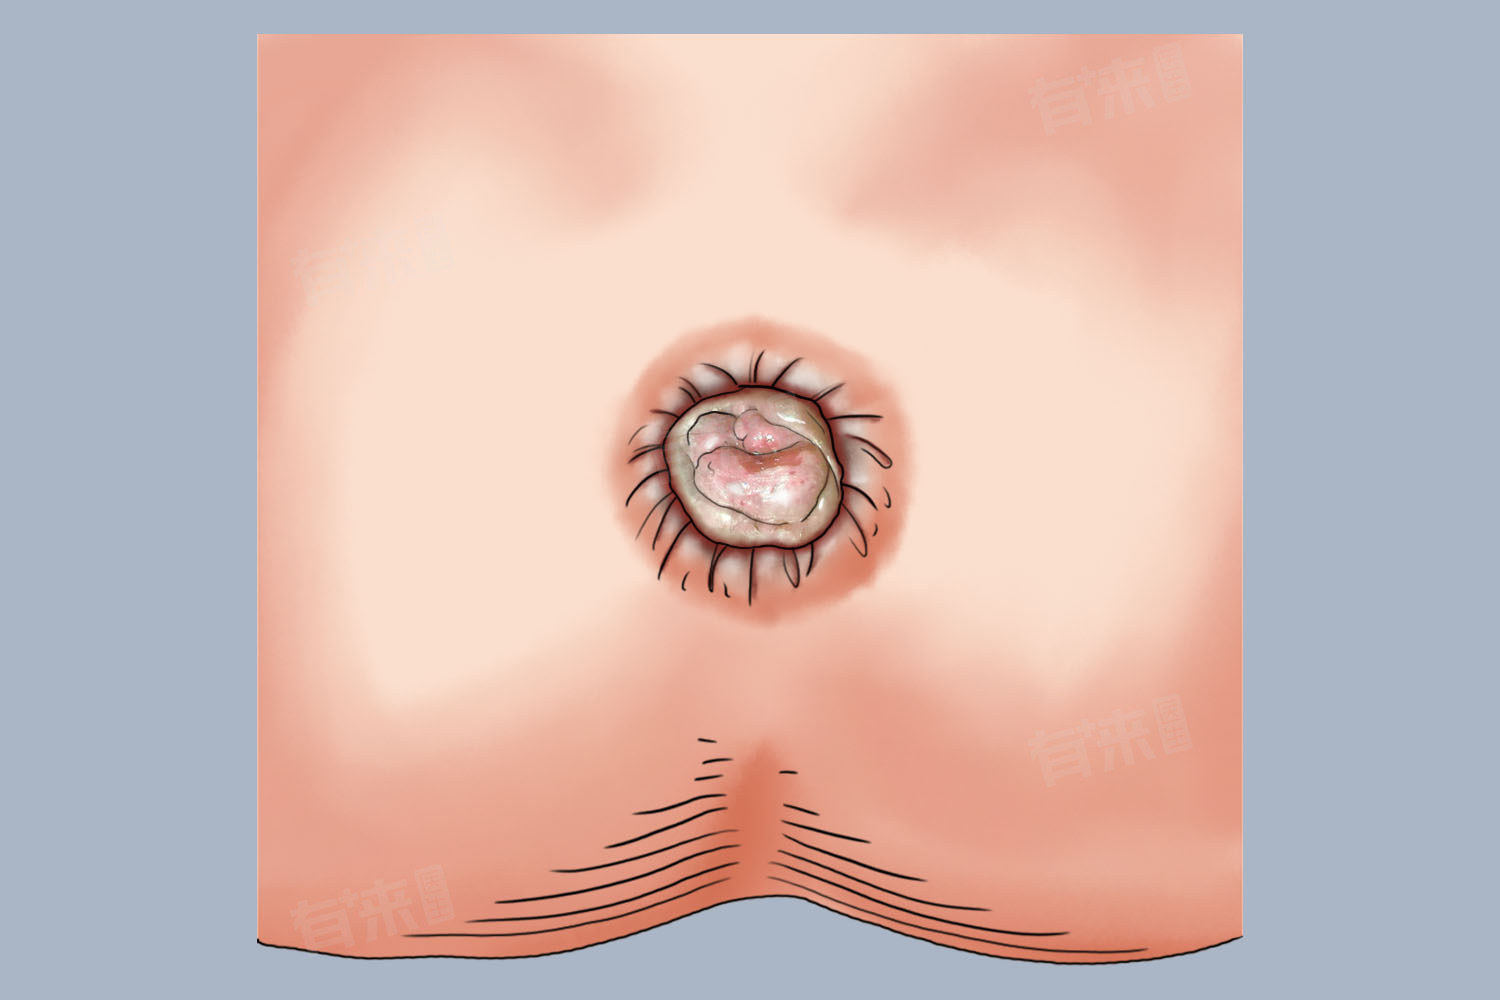

- 随着病情进一步发展,内痔的痔核不断增大,可能会逐渐呈现出球状或者分叶状。由于静脉丛持续扩张、迂曲,血液不断淤积,使得原本的小颗粒融合、膨大,当发展到一定程度后,在排便时就容易脱出肛门外,这时就能看到脱出的部分呈球状,有的还会像有多个分支的叶片一样,呈现分叶状,而且表面覆盖着黏膜组织,颜色多为暗红色或者鲜红色。

- 混合痔兼具内痔和外痔的特点,其形状也更为复杂,是内痔部分和外痔部分相互融合形成的,往往既有内痔脱出时的球状、分叶状表现,又有外痔在肛周的皮赘样或者肿块样外观,而且混合痔的范围可能更大,形态不规则,对肛门周围的形态影响也更为明显,给患者带来的不适感往往也更强。